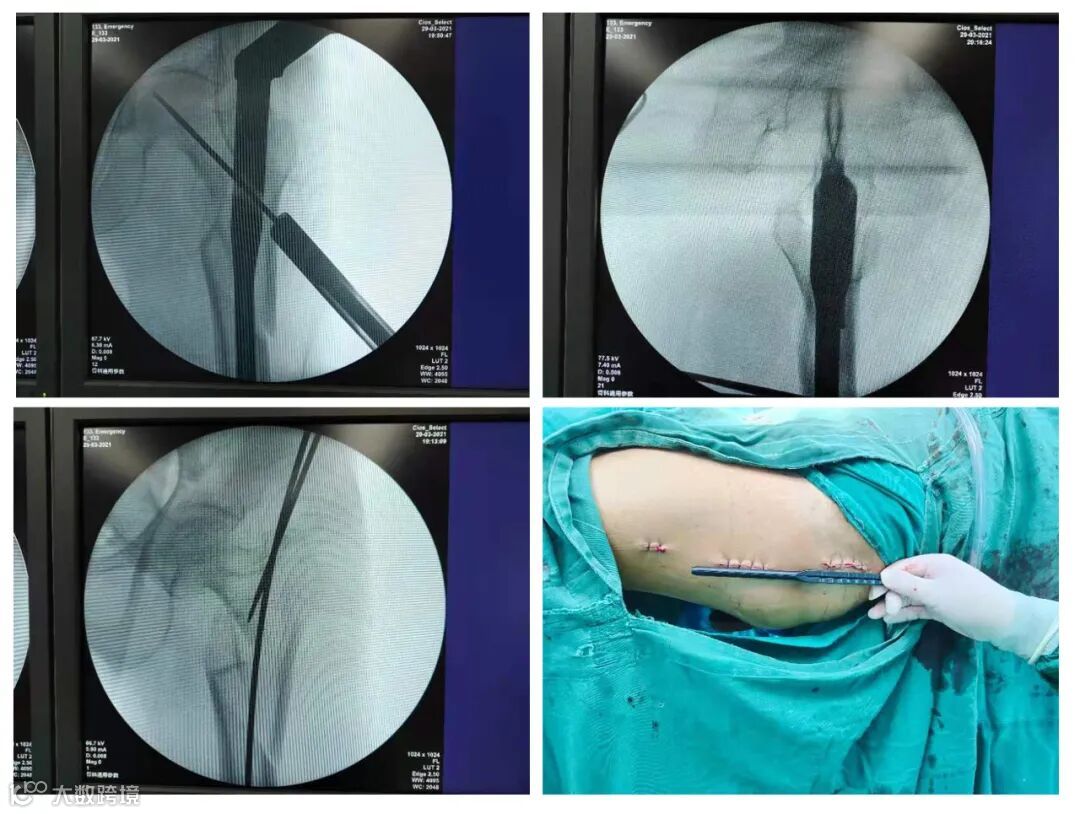

股骨转子间及转子下粉碎性骨折手术麻醉风险高、骨折并发症多、骨折粉碎程度高、复位难度大。张均锦医生在科主任朱金荣的鼓励和支持下,凭着在南方医科大学南方医院进修的临床技术积淀和近年在微创手术领域的实践(此前已经成功实施过多例高难度的骨折微创手术,临床经验比较丰富),最终在手术室、麻醉科的协助下,历经1个多小时通过三个小切口(切口最长5CM,最短2CM),顺利为患者完成骨折的微创内固定术,骨折复位情况好,术中出血极少,不需输血,切口小疼痛轻,髓内钉相比钢板具有更高的固定强度,手术圆满成功!术后林阿婆精神状态良好,第1天就能坐起并在助行器辅助下地行走。